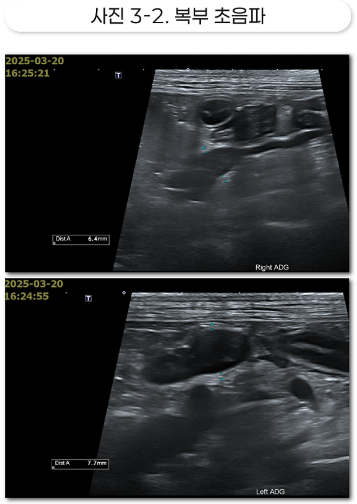

Etc: 담낭 내 슬러지 다수, 양측성 부신 비대

양측성 부신의 비대는 쿠싱 증후군의 강력한 근거.

쿠싱 증후군은 췌장염, 당뇨, 피부염, 탈모, 비만 등의 이차적인 문제를 유발할 수 있습니다.